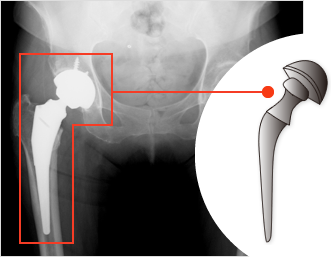

変形性股関節症

変形性股関節症は一次性(加齢や過負荷)と二次性(臼蓋形成不全や先天性股関節脱臼)によるものがあり本邦ではほとんど二次性です。変形性膝関節症よりは発症数は少ないですが関節軟骨の変性・摩耗は同様で骨変形もきたします。まずは投薬、運動療法などの保存療法を行い、症状の軽快が得られない場合は活動量や年齢を考慮して主に前方アプローチ(DAA)にて全人工股関節置換術(図5)を行っています。術後も多くの方が退院まで当院で一貫してリハビリをされています。

図5-1

変形性股関節症

図5-2

全人工股関節置換術後

図5-1

変形性股関節症

図5-2

全人工股関節置換術後